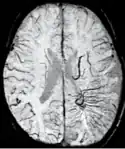

SWI Image acquired at 4 Tesla showing the veins in the brain.

Susceptibility weighted imaging (SWI), originally called BOLD venographic imaging, is an MRI sequence that is exquisitely sensitive to venous blood, hemorrhage and iron storage. SWI uses a fully flow compensated, long echo, gradient recalled echo (GRE) pulse sequence to acquire images. This method exploits the susceptibility differences between tissues and uses the phase image to detect these differences. The magnitude and phase data are combined to produce an enhanced contrast magnitude image. The imaging of venous blood with SWI is a blood-oxygen-level dependent (BOLD) technique which is why it was (and is sometimes still) referred to as BOLD venography. Due to its sensitivity to venous blood SWI is commonly used in traumatic brain injuries (TBI) and for high resolution brain venographies but has many other clinical applications. SWI is offered as a clinical package by Philips and Siemens but can be run on any manufacturer's machine at field strengths of 1.0 T, 1.5 T, 3.0 T and higher.